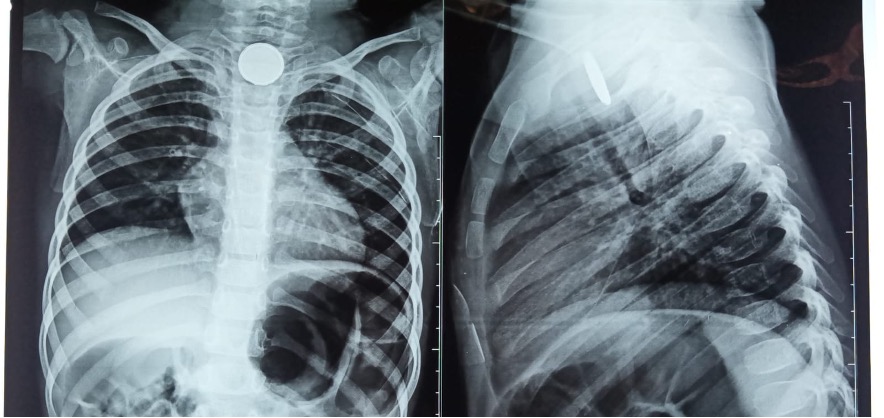

Fístula Traqueoesofágica por Ingesta de Pila de Botón ¿Manejo Conservador?

Arturo Emilio Guerra Rodríguez, Manuel Alfredo Medellín Vázquez, Jesús Eduardo Treviño Alvarado, Carlos Alberto Zapata Castilleja, José Guillermo Martínez Flores